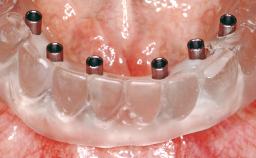

Immediate Loading of Two Implants in the Mandible and Final Restoration with a Bar-Supported RDP

A 56-year-old female patient was referred to the clinic because of retention problems with her mandibular denture. She had been completely edentulous for more than 33 years and wore her sixth set of complete conventional dentures, which had been delivered 5 years previously. An oral surgeon had performed a vestibuloplasty in the interforaminal region of the mandible with a piece of skin tissue 12 years earlier. The panoramic radiograph and lateral cephalometric radiograph exhibited the hypotrophy of the inferior alveolar process. The mandible was a Cawood class VI,and the height of the mandible in the interforaminal zone was 15 mm.